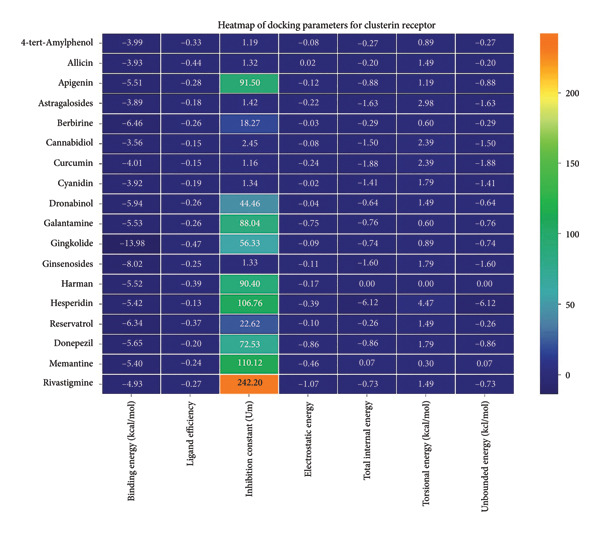

3.3. AutoDock Vina Results: Clusterin Receptor

Ginkgolide showed the strongest binding at −13.98 kcal/mol, interacting with HIS205. Other potent ligands were ginsenosides (−8.02 kcal/mol), which formed contacts with PHE240, and berberine (−6.46 kcal/mol), interacting with ASN291. Resveratrol also exhibited favorable binding (−6.34 kcal/mol), forming H‐bonds with PRO212 and ALA373. Cannabidiol had the weakest binding at −3.56 kcal/mol, interacting with ARG292:HE1. The weakest binder was cyanidin (−3.92 kcal/mol), which showed no hydrogen bond interactions.

For reference drugs, donepezil (−5.65 kcal/mol) with GLY378, Figure 3 illustrates the binding characteristics of natural ligands and reference drugs for the clusterin receptor.

The heatmap in Figure 6 provides a comprehensive visual interpretation of the AutoDock Vina docking analysis of natural ligands (light blue‐coded) and reference drugs (orange‐coded) against four key AD‐related receptors. Ginkgolide consistently demonstrates strong (deep red coloration) binding energies across all four receptors: sortilin (blue‐coded), clusterin (green‐coded), Aβ peptide (yellow‐coded), and tau proteins (purple‐coded). Natural ligands exhibited varied yet significant binding profiles; ginsenosides showed strong affinities for tau proteins and Aβ peptide, with moderate binding to sortilin and clusterin. Dronabinol displayed particularly strong interactions with sortilin and Aβ peptide, while berberine and apigenin consistently showed favorable binding across multiple targets, underscoring their broad spectrum of action. In stark contrast, hesperidin consistently presented among the weakest binding affinities across most receptors (indicated by blue/lighter colors), suggesting limited direct molecular interaction.

Comparative analysis against the established reference drugs—memantine, donepezil, and rivastigmine—revealed that several natural compounds, most notably ginkgolide, achieved binding affinities that were superior to these therapeutic agents across various AD‐related targets, highlighting their significant potential as alternatives or adjuncts. The hierarchical clustering patterns displayed by the dendrograms provided further insights: Molecules grouped together along the y‐axis (ligand–receptor pairs) often shared similar overall binding characteristics. For example, ginkgolide consistently clustered within highly favorable binding groups across multiple receptors (Figure 7), and groups like ginsenosides and cyanidin showed similar strong binding patterns toward tau proteins. Notably, certain natural ligands, such as allicin and harman, clustered with other smaller, more drug‐like natural compounds. Importantly, this clustering also revealed instances where natural ligands exhibited similar binding profiles to reference drugs like memantine, donepezil, or rivastigmine, suggesting potentially shared binding modes or therapeutic mechanisms.